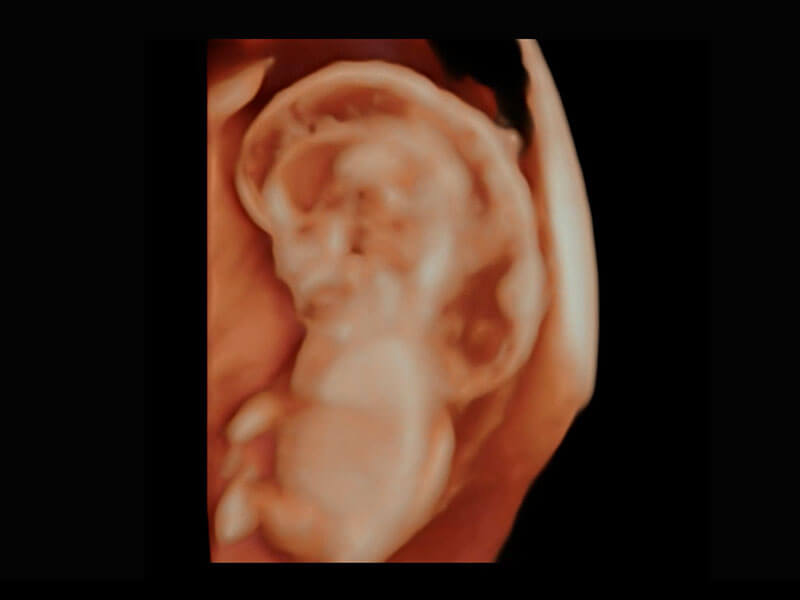

P60在胎儿早孕期超声筛查中为您带来优异的图像质量。

P60提供简单易学易用的高端诊断工具,为您中晚孕筛查提供快速清晰的解剖信息。